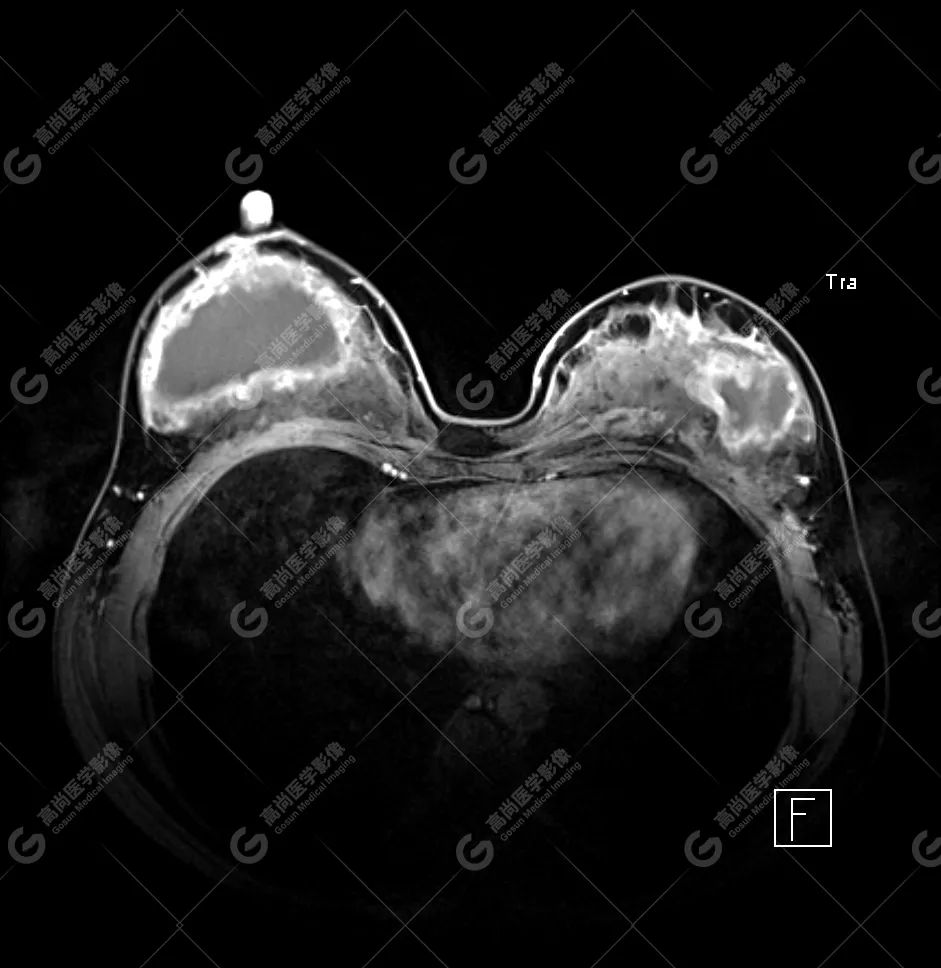

病例 4:乳腺注射物部分取出术后,后硅胶假体植入术后 3 年余

双侧假体包膜不光整,包膜下可见多发线样低信号影,左侧假体内可见「面条征」——双侧假体内包膜破裂(部分破裂)